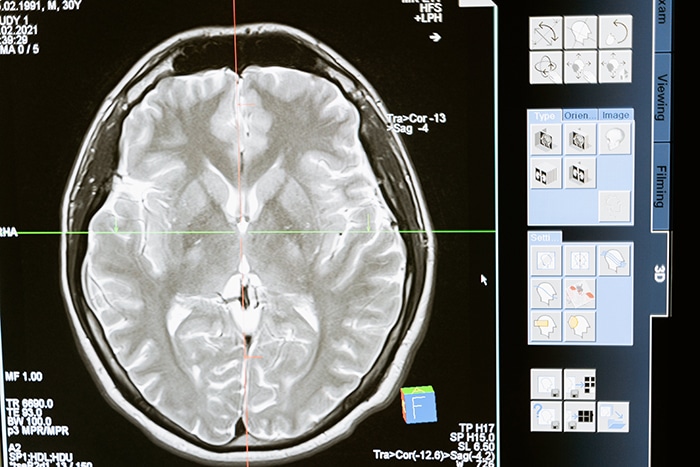

Dreaming Promotes Brain Health

Most dreams are relatively short but have significant effects on mental function and brain health.

Researchers believe that dreaming consolidates memories while helping people manage stress, anxiety, and other negative feelings or emotions. Moreover, it can enhance creativity and cognitive function, says the University of California, Berkeley.